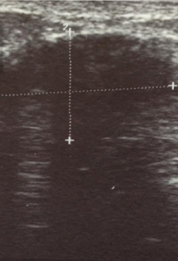

Υπερηχογράφημα ανδρικού μαστού. Πορογενές καρκίνωμα (Ευγενική παραχώρηση Dr. V. Penopoulos)